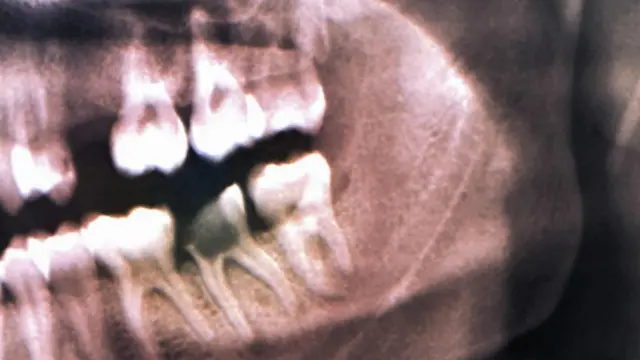

İncelenen kemiklerden biri, 100 yıl önce Slovenya yakınlarında bir mağarada bulunan ve 6500 yıl öncesine ait olan bir insan çenesiydi.

Dişlerden birine yapışık ilginç bir madde araştırmacıların dikkatini çekmiş, bunun dişteki oyuğu doldurmak için kullanılmış balmumu olduğu görülmüştü.

Bugün bu kafatası İtalya’daki Trieste Doğal Tarih Müzesi’nde sergileniyor ve yeryüzünün en eski dolgusu büyük ilgi görüyor.